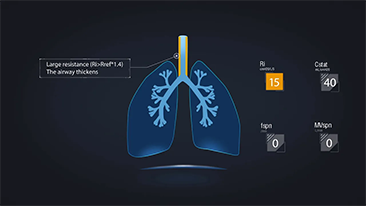

Solunum yolu hastal??? olan hastalar?n tedavisi i?in do?ru ventilat?r ayarlar?n?n se?ilmesi, olduk?a ?nemli bir konudur. Ventilasyon ekipman?n?n parametrelerini belirleme g?revi b├╝t├╝n├╝yle bir hekim taraf?ndan yap?ld???ndan, hekimin bu ayarlar?n se?imindeki bilgisi ve deneyimi, verece?i kararlar?n do?rulu?u ├╝zerinde do?rudan etkilidir. Hastalar?n destekleyici bak?m? paradigmas?, son 20 y?lda ?nemli ?l?├╝de de?i?ti. G├╝n├╝m├╝zde, bak?c?lar?n klinik kararlarda verimlili?i art?rmas?na ve hatalar? ortadan kald?rmas?na yard?mc? olmak i?in, klinik gereksinimler etraf?nda ?e?itli ventilasyon modlar? ve karar destekleme ara?lar? geli?tirildi.

Y├╝ksek ak??l? oksijen tedavisi, invaziv olmayan ventilasyon ve invaziv ventilasyonu entegre eden 3'├╝ 1 arada SV Serisi ventilat?rler, istikrarl? performans ve ?ok y?nl├╝ fonksiyonlar ile kullan?m kolayl???n? bir araya getirir. Ola?an├╝st├╝ akci?er koruyucu ?zellikleri ve bir?ok karar destek arac?, ?apraz enfeksiyon riskini azaltmak ve bak?c?lar?n g├╝nl├╝k rutinini kolayla?t?rmak i?in tasarland?.